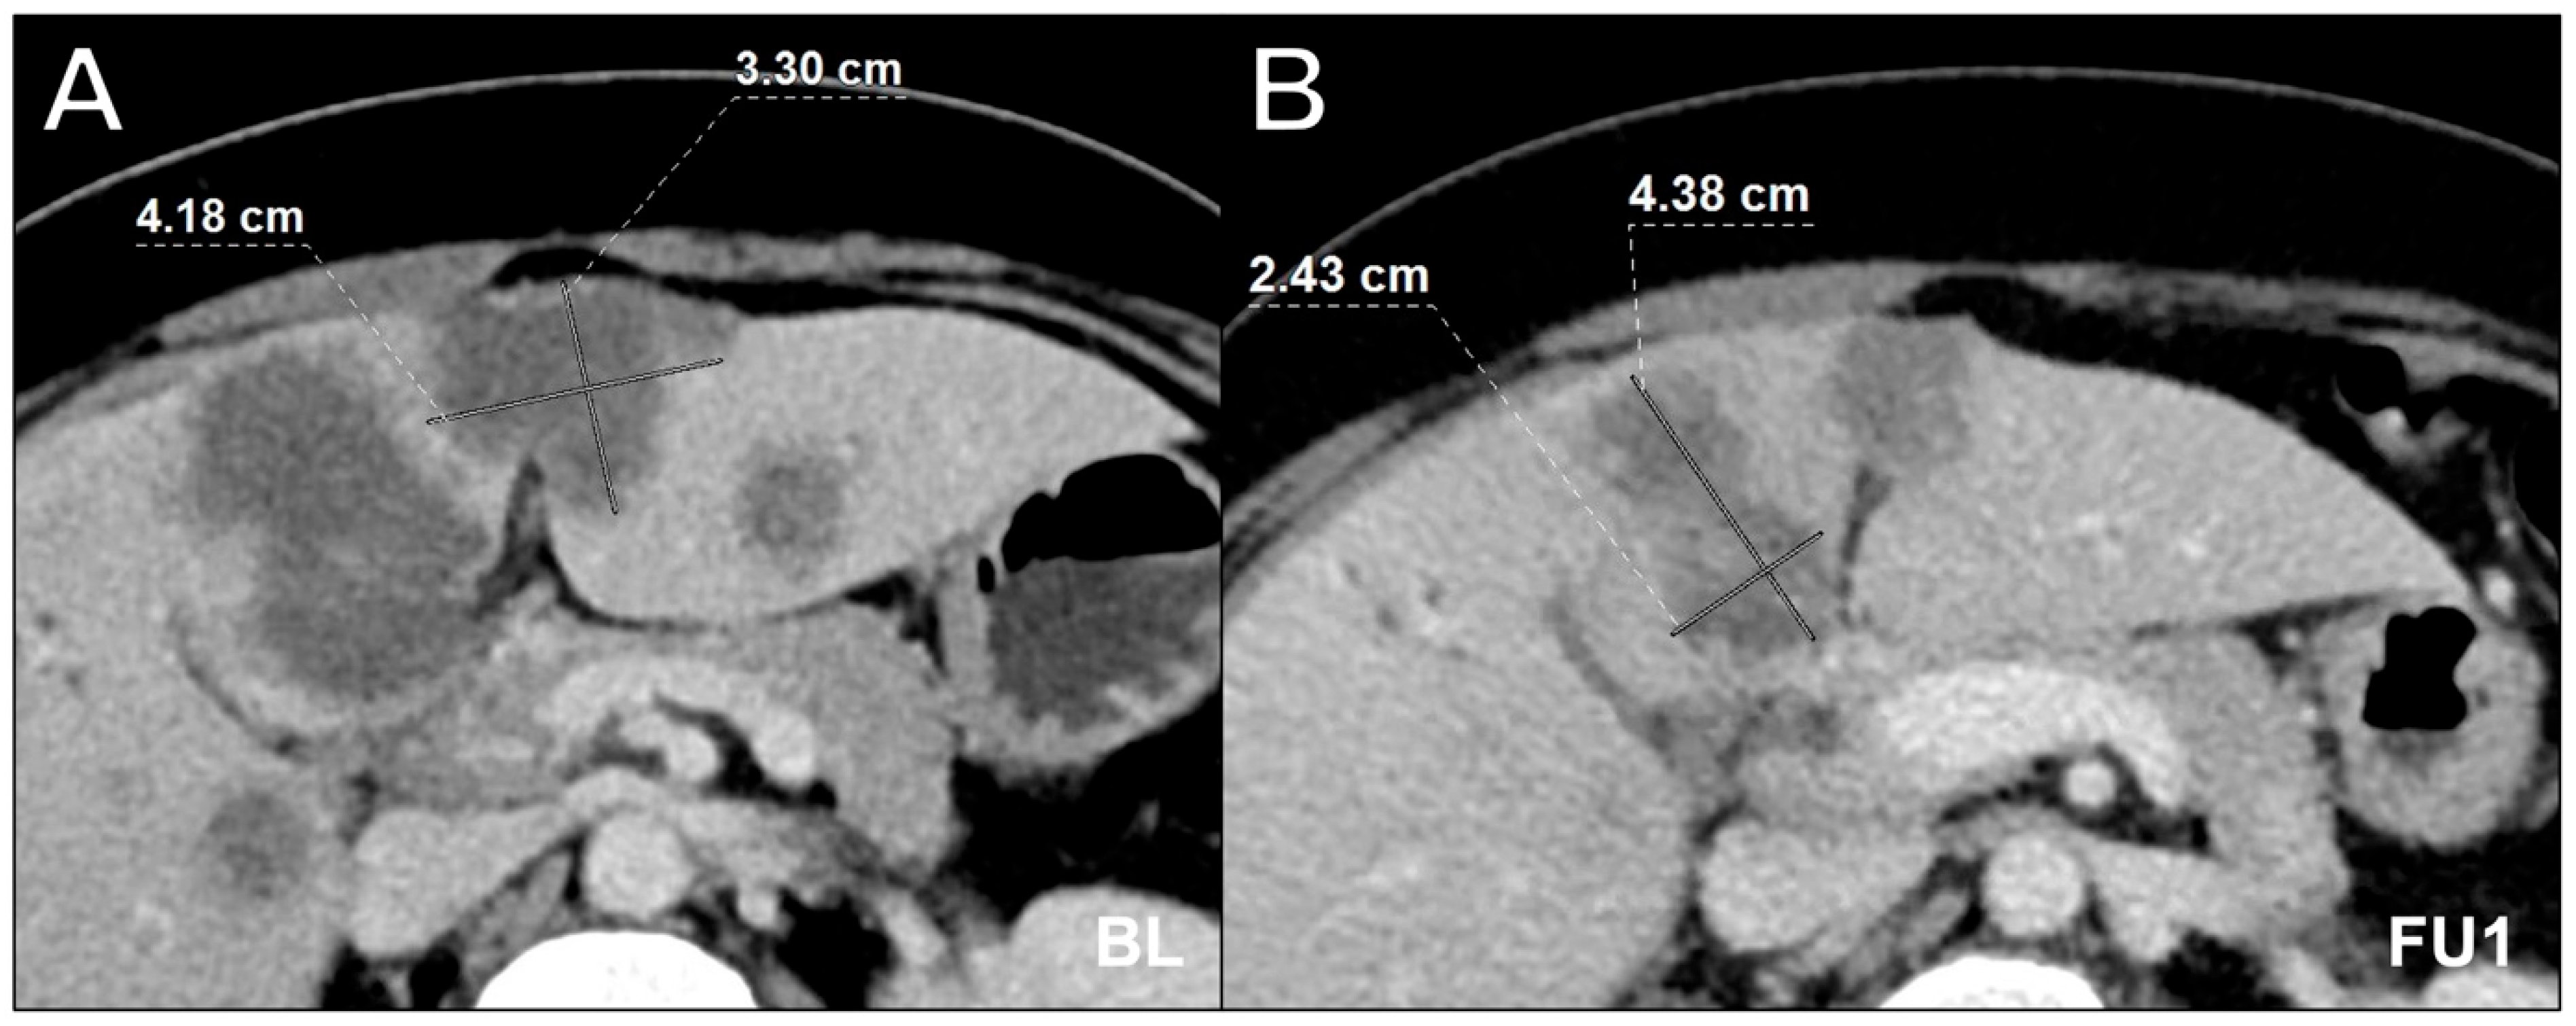

Figure 3.

Axial contrast-enhanced computed tomography scan in portal venous phase in a 64-year-old male with multiple hepatic metastases in colorectal carcinoma at baseline (A) and follow-up 1 (B) showing incorrect lesion assessment at follow-up 1. Appropriate documentation is essential, especially when there are multiple target lesion candidates. While the software-assisted approach offers side-by-side assessment with structured lesion documentation, reader 3, who performed the manual assessment, mixed up lesions at follow-up 1, resulting in an incorrect overall response compared to the consensus reading. It is likely that the presentation state was not correctly stored in the PACS when the baseline measurement of the lesions was performed. BL = baseline, FU1 = follow-up 1.